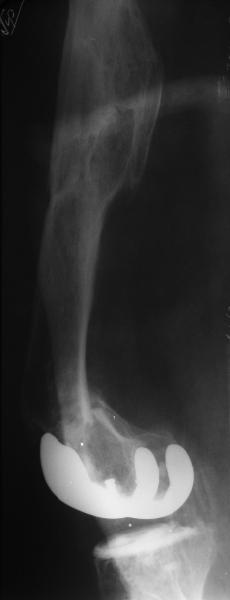

Видимо, самое "модное" на сегодня - малоинвазивный остеосинтез пластиной с угловой стабильностью. Распространенный вариант и закрытый интромедуллярный остеосинтез ретроградно. Хотя у нас было бы сделано антеградно - лешево и сердито, действительно малоинвазивно, в сустав не надо влезать. Нет риска прорезания порозной кости с миграцией в сустав, что возможно при ретроградном - гвоздь вводится через вырез в бедреннм компоненте, туда же может и вывалиться. А антеградный - упрется в протез. Как раз вчера заходил больной через полтора года после такой операции. Снимки в приложении.